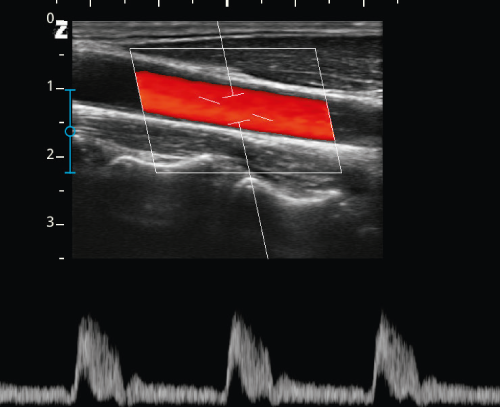

USG skóry, działające na częstotliwościach do 20 MHz, pozwala na szczegółowe obrazowanie powierzchownych warstw skóry, co jest kluczowe przy ocenie tkanki przed zabiegami modelującymi. W zależności od potrzeb klinicznych, ultrasonografia umożliwia monitorowanie głębokości tkanki tłuszczowej, oceny struktury skóry oraz określenie poziomu nawilżenia, a także precyzyjnej analizy efektów terapeutycznych w czasie rzeczywistym.